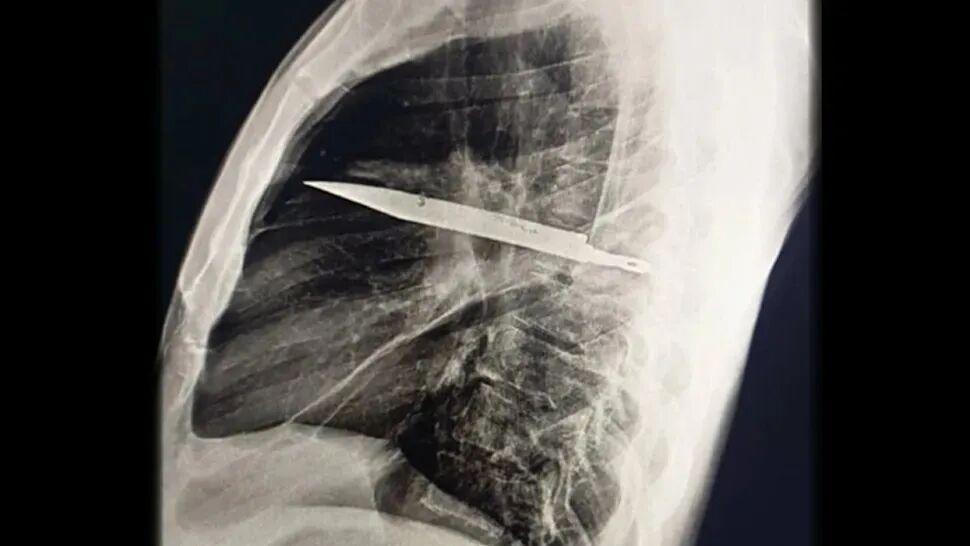

一位44歲的坦桑尼亞男子成了今年最令醫生震驚的狠人:他胸腔裏插着一把刀生活了8年,自己竟然渾然不覺[2]

一把刀幾乎貫穿了患者的右側胸腔,並從他的肺葉中間穿過,但他竟然在8年間對此渾然不覺。| Kivuyo et al.

直到這位患者因爲傷口流膿前來就醫,醫生才通過X光檢查發現了這個驚人的祕密。檢查顯示,從把手上脫落的金屬刀刃幾乎貫穿了患者的胸腔。在手術取出刀片、清除壞死組織之後,男子順利痊癒。

患者8年前曾捲入一場暴力衝突,刀子就在那時進入了他的身體。人體內的異物周圍常會形成纖維囊包裹,可能正是這種包裹限制了炎症與組織損傷,讓患者沒有察覺刀的存在。

醫生強調,刀片滯留和當地醫療資源的匱乏密切相關。如果患者受傷時能進行全面檢查,就不會留下這種隱患。